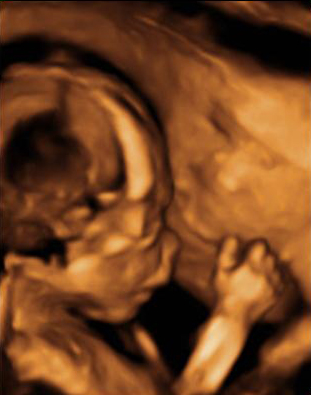

En la ecografía en 4D de un feto de 18 semanas de embarazo se ve la cara ya armonizada: las orejas y los ojos que en un principio estaban desplazados, ya se encuentran en su lugar, lo que le da una imagen mucho más "humana".

Ecografía de la cara de un bebé de 18 semanas

A esta edad temprana, apenas 20 semanas de gestación, las estructuras faciales básicas están prácticamente conformadas.